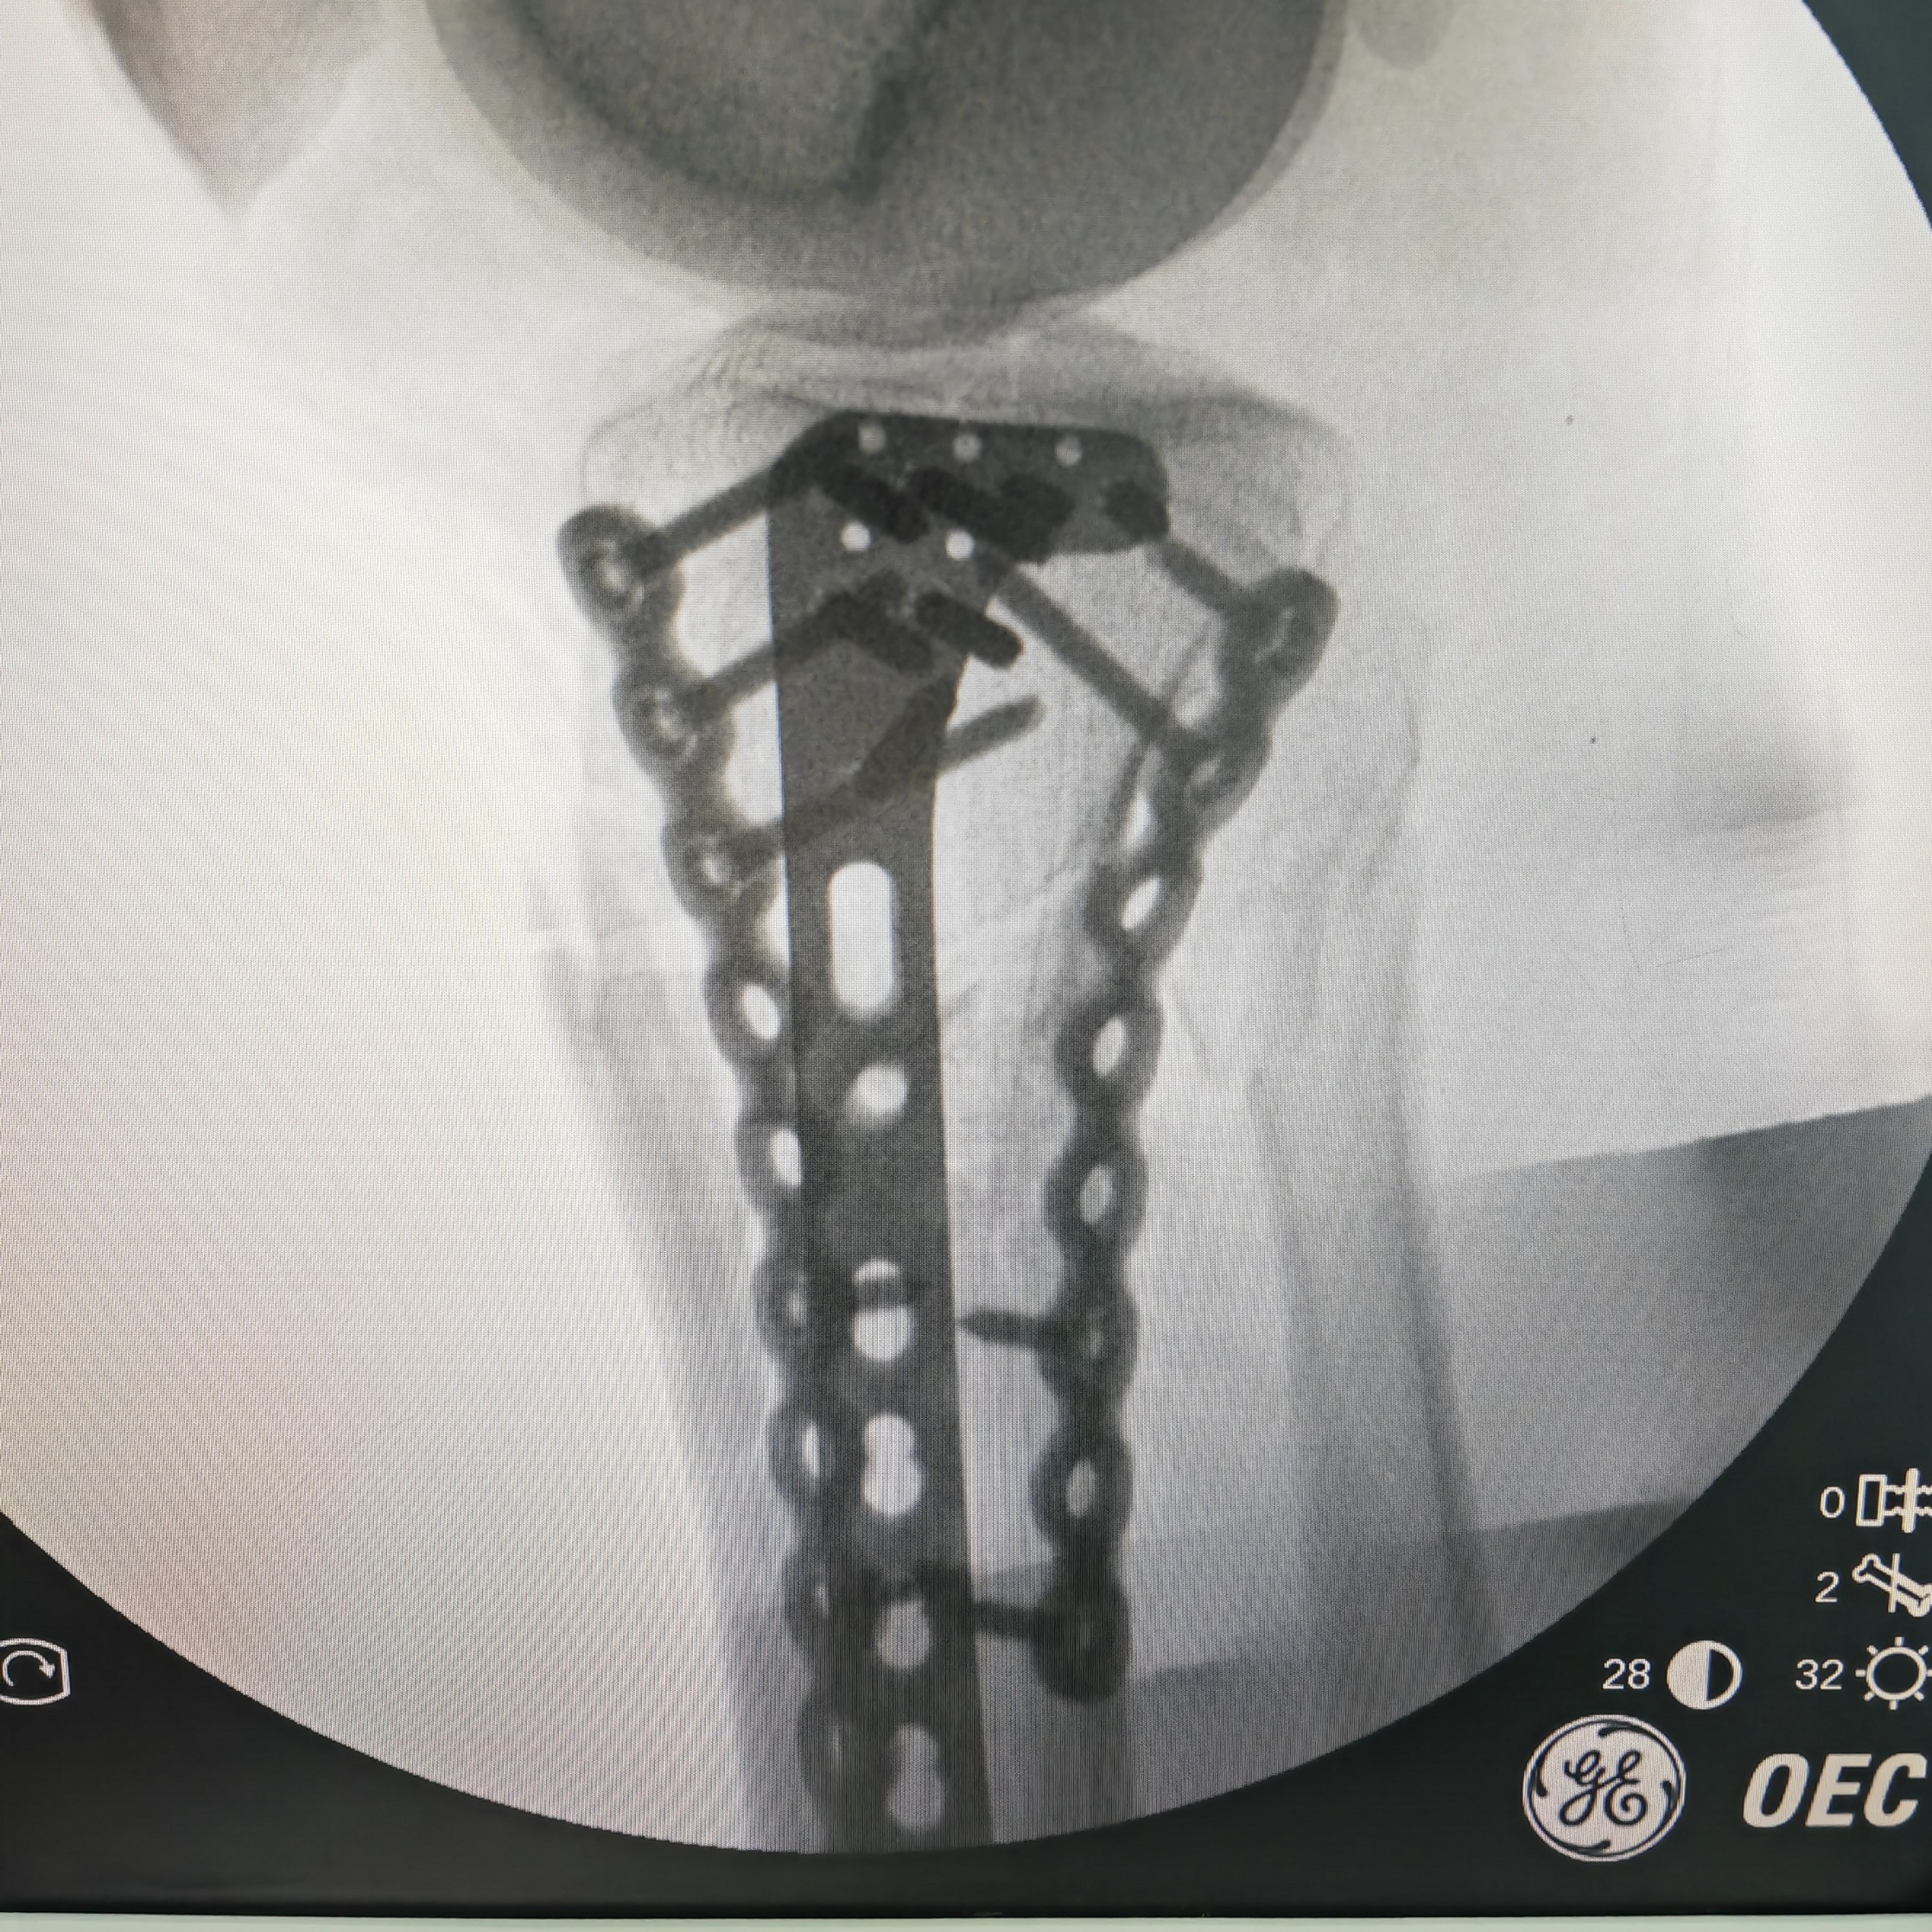

【治疗经过及结果】:入院后完善检查,行手术治疗。术中发现中央束止点断裂,桡侧侧腱束末节止点断裂,桡侧及掌侧关节囊断裂,予以锚钉修复,克氏针固定